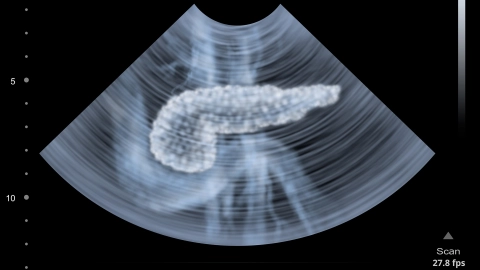

An Bauchspeicheldrüsenkrebs erkranken pro Jahr etwa 20.000 Menschen in Deutschland. Der Tumor wird häufig erst spät entdeckt. Dementsprechend ungünstig sind die Heilungschancen.

Ist die Bauchspeicheldrüse akut entzündet, führt das zu sehr starken Schmerzen, die ganz plötzlich auftreten. Oft sind Gallensteine der Auslöser.